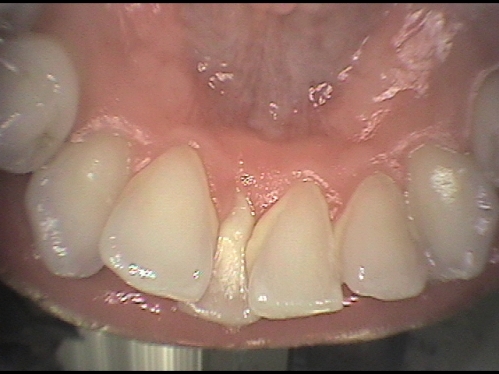

Les dents qui se chevauchent

Des dents qui se chevauchent sont souvent plus difficiles à nettoyer.